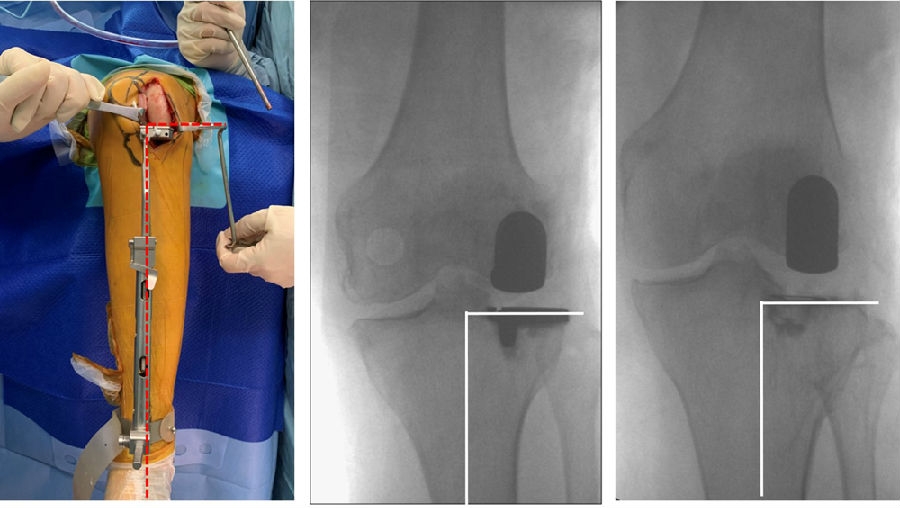

关键技术2:截骨厚度2-3mm

外侧OA多发生在股骨侧,常伴有外侧股骨髁发育不良。通常需要做内翻应力位判断外侧间隙张开程度及胫骨磨损程度。

胫骨截骨应尽可能保守,通常2-3mm即可,以利用胫骨近端皮质的强度,并可增大承载面积。

关键技术3:水平截骨-无内外翻

胫骨截骨导杆与胫骨前缘平行(冠状面),此时无内外翻。

关键技术2:恢复关节线

重建关节线意义重大,因为关节线的抬高可能导致不稳定。

可能引起抬高关节线的操作:通过过度研磨股骨远端,试图匹配屈伸间隙;通过在屈曲位选择垫块厚度导致外侧间室过度填塞。

外侧间室在自然屈曲状态下松弛,将允许更厚的胫骨垫片插入,所以LUKA应在伸直位选择垫片厚度,从而达到平衡

关键技术3:理想的下肢力线

HIP-Knee-Ankle line 外翻3-5°,胫骨角10-12°

LUKA 术后畸形矫正不足,保持轻微的外翻。建议LUKA术后保留3 ~ 5°外翻。